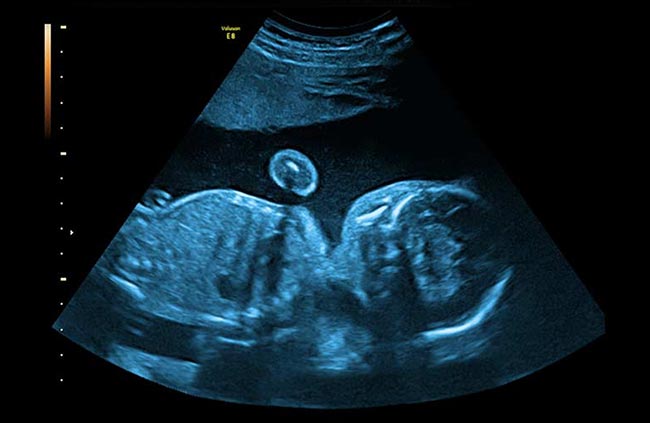

作為一名婦科醫生,Radovan Marek經常詳細檢查胎兒的圖像。“我需要將胎兒探索從最高質量的超聲波機器轉移到計算機上進行檢查,”他解釋道。

馬雷克指出,他將捕獲的超聲影像存儲在他的計算機中,在那里他能夠詳細檢查它們并做出“最高質量的區別”。